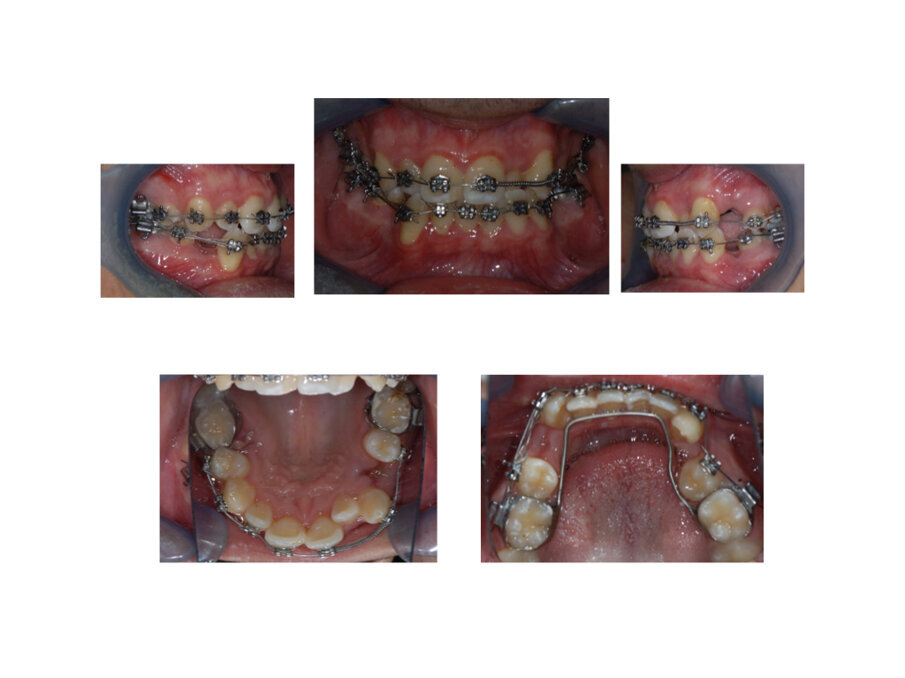

Materiali e metodi

L’estrazione dei primi premolari mandibolari 3.4 e 4.4 è la prima fase terapeutica durante la gestione di un caso ortodontico estrattivo. La differente conformazione ossea con una maggior componente corticale pone anticipata l’estrazione dei premolari mandibolari. Successivamente a distanza di 1 mese si programma l’estrazione dei premolari mascellari. Gli elementi dentali in questa fase iniziale chirurgica sono liberi ad eccezione dei primi molari inferiori a cui viene ancorato un arco linguale. Tale arco ha la funzione di contribuire a una migrazione spontanea distale dei canini mandibolari 3.3 e 4.3 evitando però una traslazione mesiale del gruppo diatorico inferiore. Durante la guarigione post estrattiva dei premolari a livello maxillare prende inizio la terapia biomeccanica secondo metodica straight-wire (Fig. 3). La sequenza degli archi che è stata utilizzata sono: .014 NiTi, .016 NiTi, .016 x .016 NiTi, .020 x .020 NiTi, .016 x .022 Stainless Steel and .019 x .025 Stainless Steel. Dopo i primi mesi di terapia ed eseguita l’iniziale fase di allineamento, tramite l’uso di archi in acciaio rettangolari posted si attua la chiusura dei spazi estrattivi tramite molle chiuse in NiTi da 250 gr di forza (Fig. 4) Lo spazio estrattivo è stato chiuso dopo sette mesi di terapia. A termine della rifinitura ortodontica il caso ortodontico è terminato dopo 24 mesi di terapia complessiva.